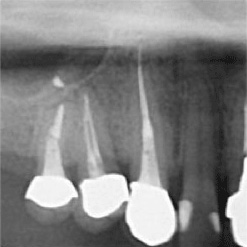

当院で処置した症例をご紹介します。

他院で抜歯と言われてしまった歯でも抜歯せずに対処した症例も多数あります。

黒い影が出ている部分が問題の個所で(根尖病巣)、治療後はこの影がなくなっているのが見て取れると思います。

保険適用。根尖病巣を治療した症例。リスクとして、稀ではありますが再発することがあります。